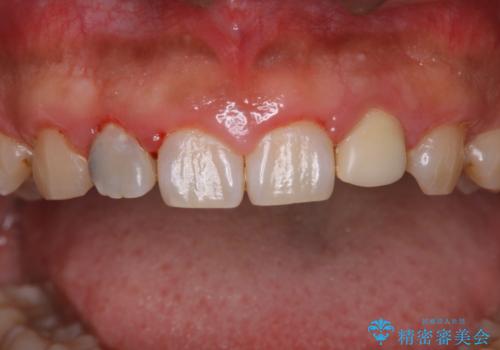

PMTC60分コースを行いました。

20年ぶりのクリーニングということもあり、歯の表面全てにプラークが付着していました。

プラークの細菌によりかなり歯ぐきが腫れていました。1度のクリーニングで汚れは落とせますが、このまま何もしないとまた同じようにプラークが付着し、それを繰り返すことになるだけでなく、歯周病や虫歯が進行してしまいます。そうならないためには、日々のケア、ホームケアがとても大事になっていきます。